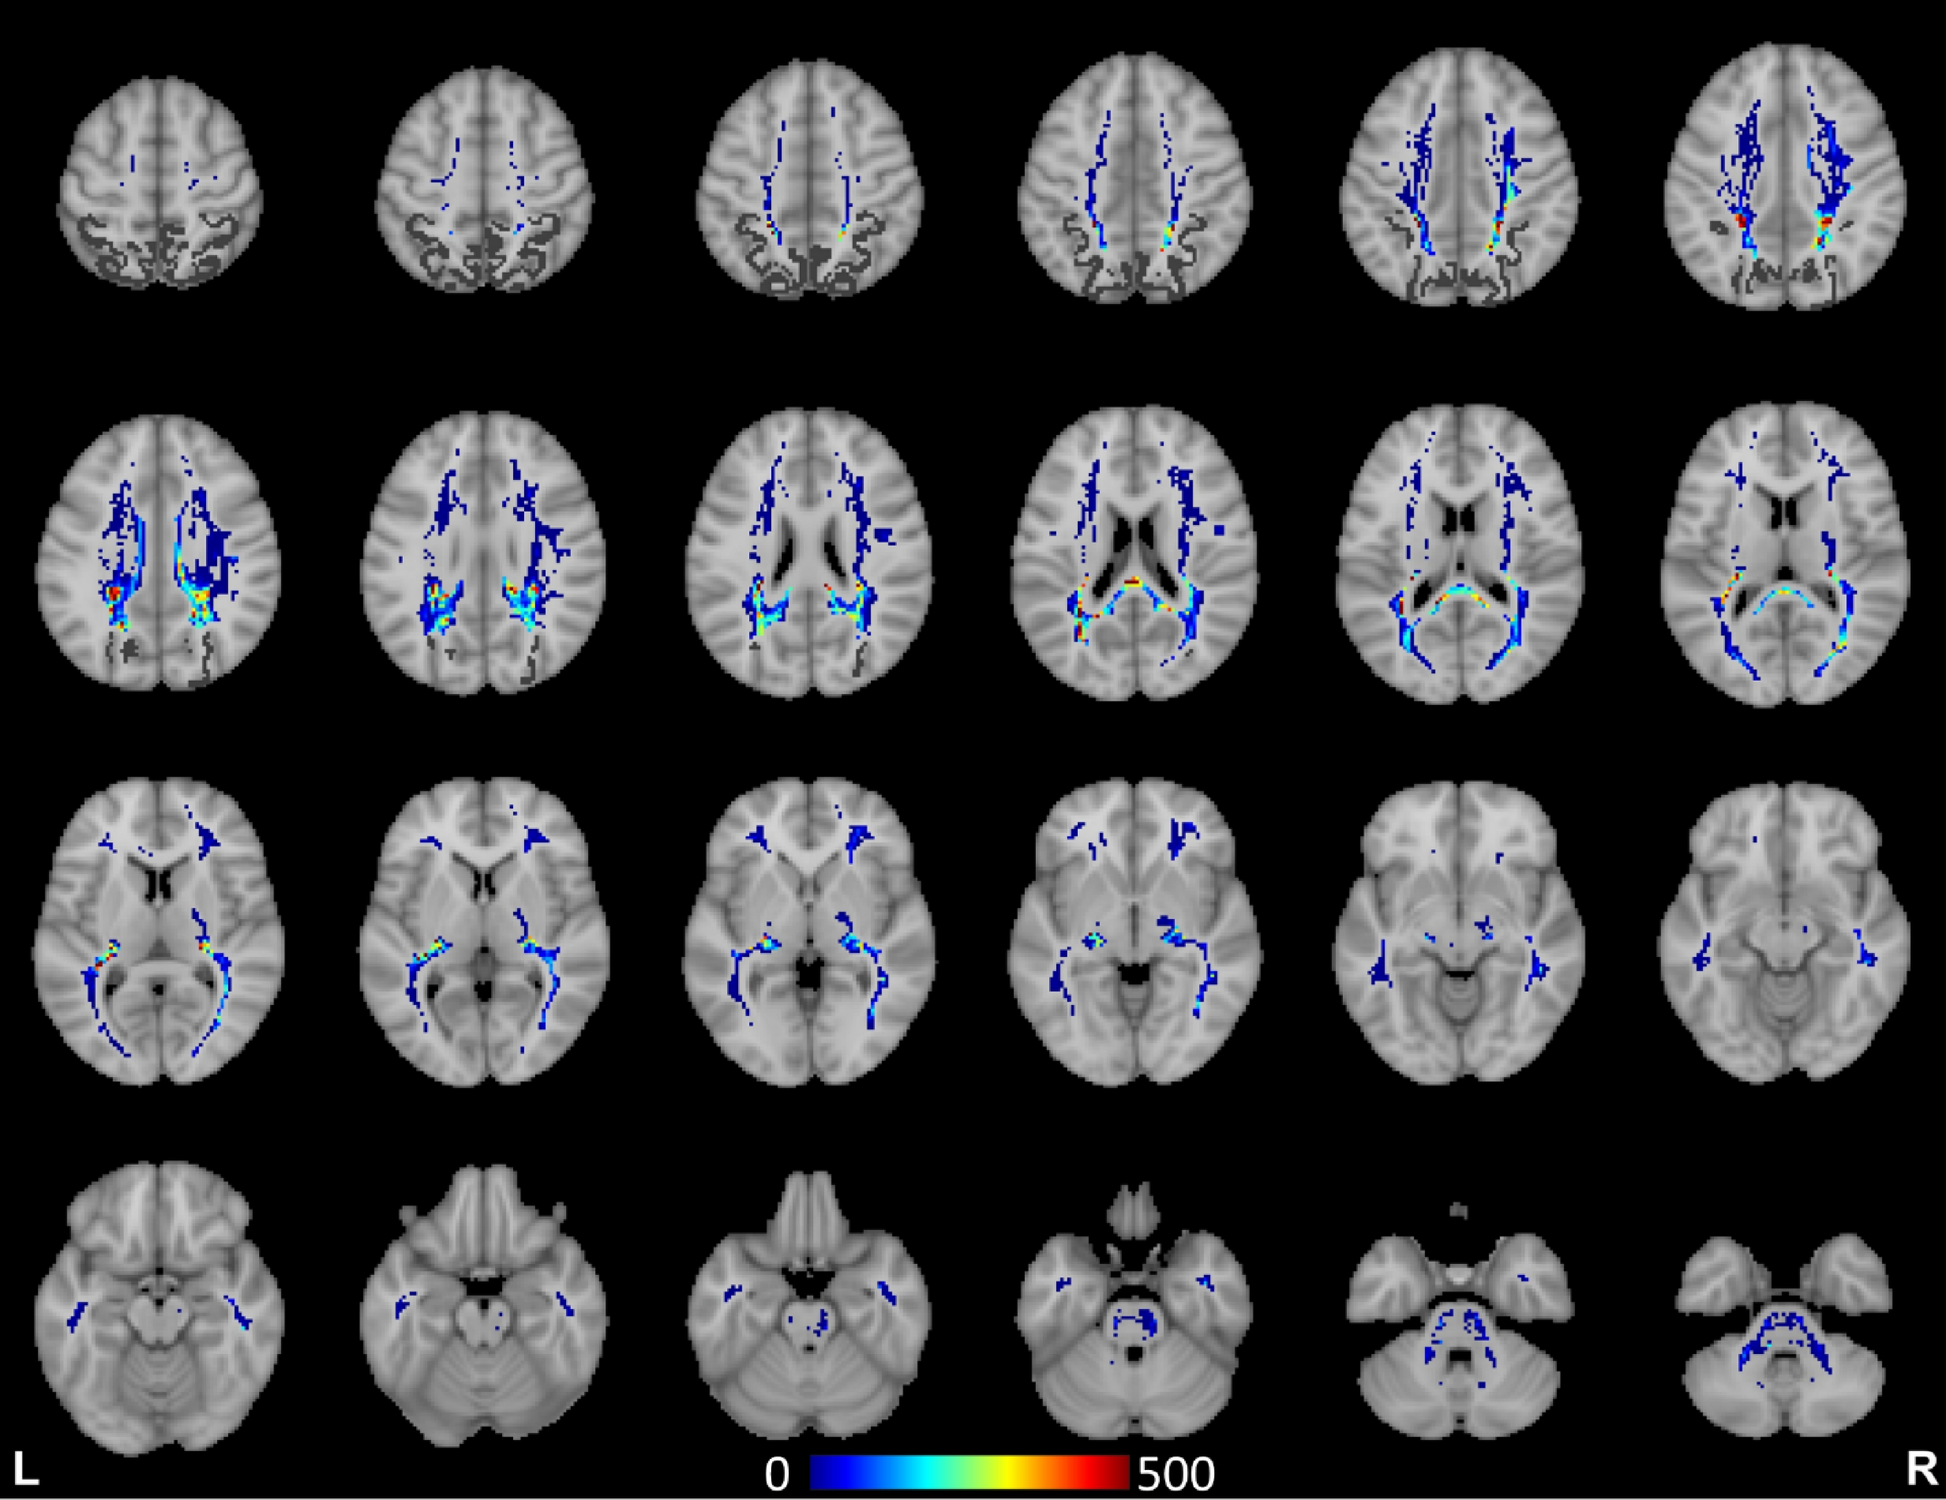

Spatial maps of white matter structural connectivity to Brodmann Area 7. The color is scaled to the number of fiber tracts in each voxel.

Fig. 7